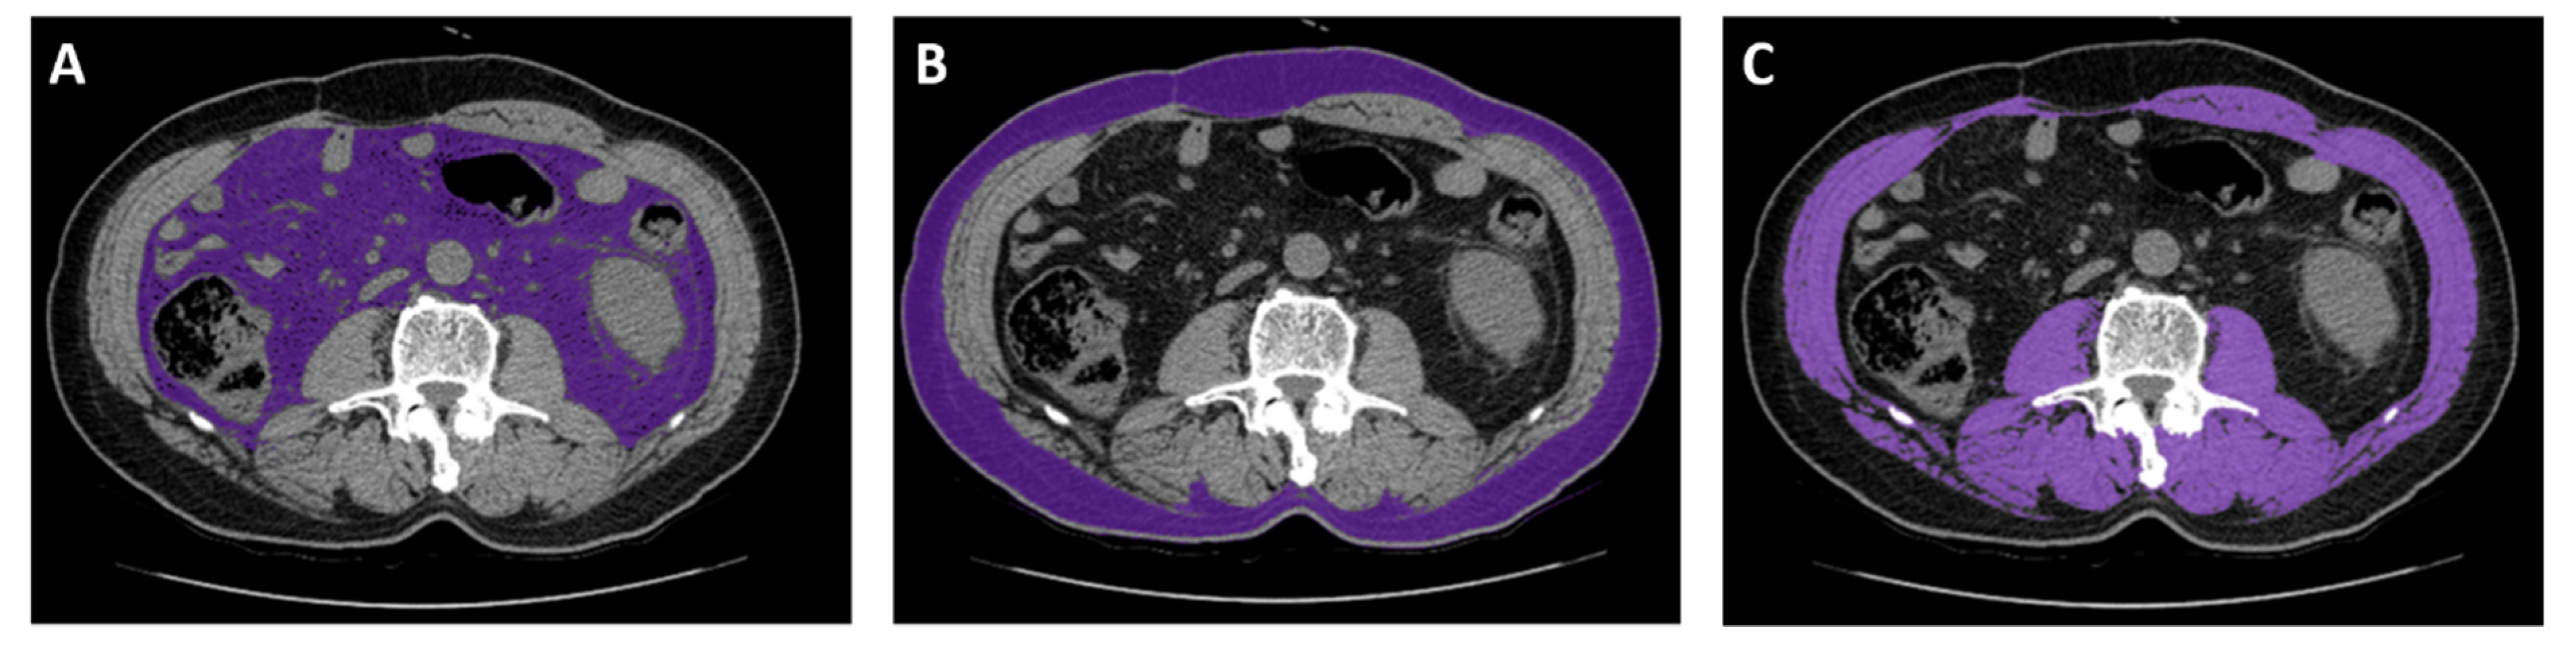

4.3. Anthropometry and Body Composition

4.4. Image Analysis